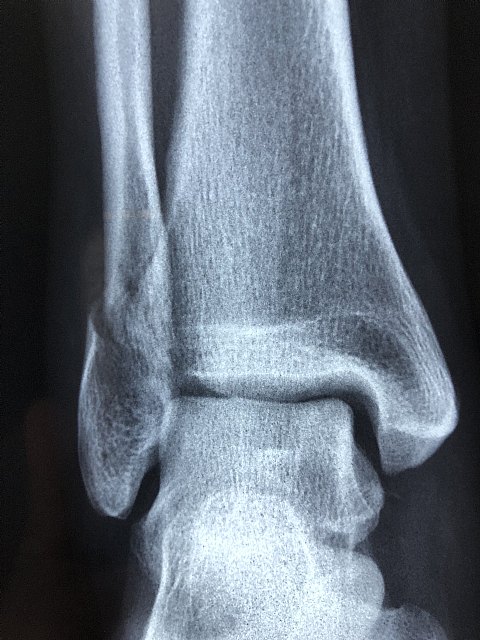

En el caso de que el esguince sea leve –grado I-, se manifiesta con dolor, hinchazón leve y, en algunas ocasiones, un ligero moratón, pero no se pierde movilidad en el tobillo y la persona es capaz de caminar, ya que el ligamento solo se ha estirado demasiado o roto ligeramente (menos del 5% de las fibras). Si hay un desgarro o rotura parcial del ligamento -grado II-, aumentan el dolor, la inflamación, el hematoma puede ser mayor y la movilidad del tobillo puede verse limitada. También puede resultar difícil apoyar peso sobre el pie, lo que resulta imposible en caso de esguince severo -de grado III-, consecuencia de una rotura o desgarro total del ligamento (que cursa además con gran inflamación y hematoma muy evidente).